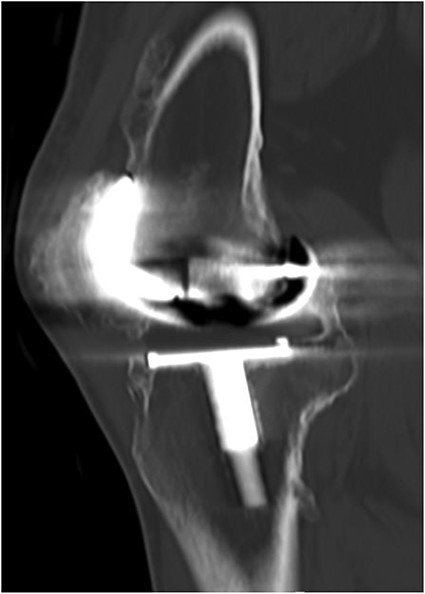

CT demonstrated extensive heterotopic ossification involving the popliteal fossa, the anterior surface of the patella and at the distal third of anterior femur extending to the level of the knee-replacement prosthesis. There was no evidence of implant looseness or alignment deformity and there was no evidence of progressive ossification.